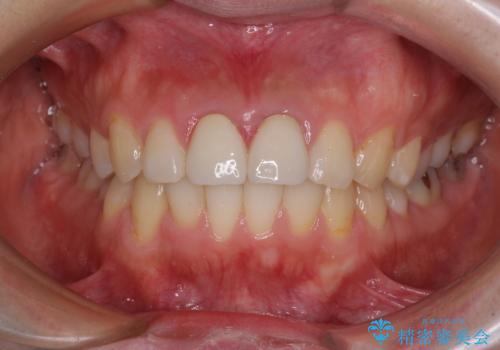

下顎前歯の部分矯正に半年ほどかかってしまい、少し期間は長いものとなりましたが、上下ともに前歯がきれいに整い、患者様には大変満足していただきました。